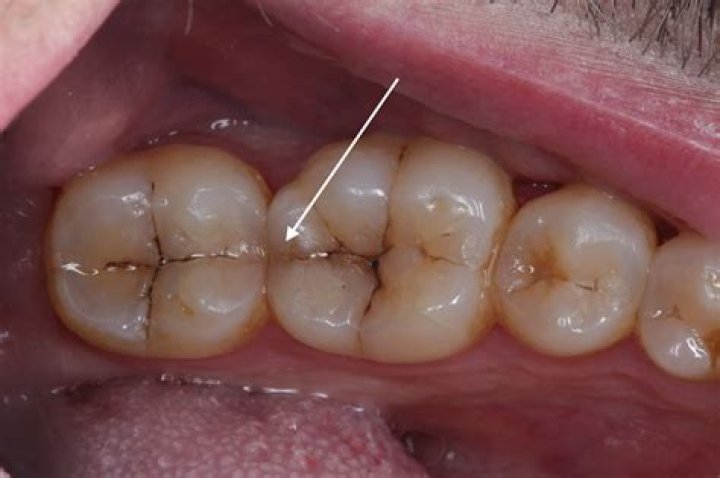

Can I live with a cracked tooth?

Sure, you can probably live with a cracked tooth. There may be minimal pain and it might not even show when you smile-but there are many dangers to living with a fractured tooth that could affect your oral health for years to come. A tooth can crack/fracture when there is a weak spot or trauma to the tooth.

What can a cracked tooth lead to?

If they are not treated, cracked teeth can lead to the death of the nerve, and an abscess might grow. The tooth could need root canal treatment or even taking out. In severe cases the tooth can actually split in two. If this happens your dentist will not be able to save the tooth and it will need to be taken out.